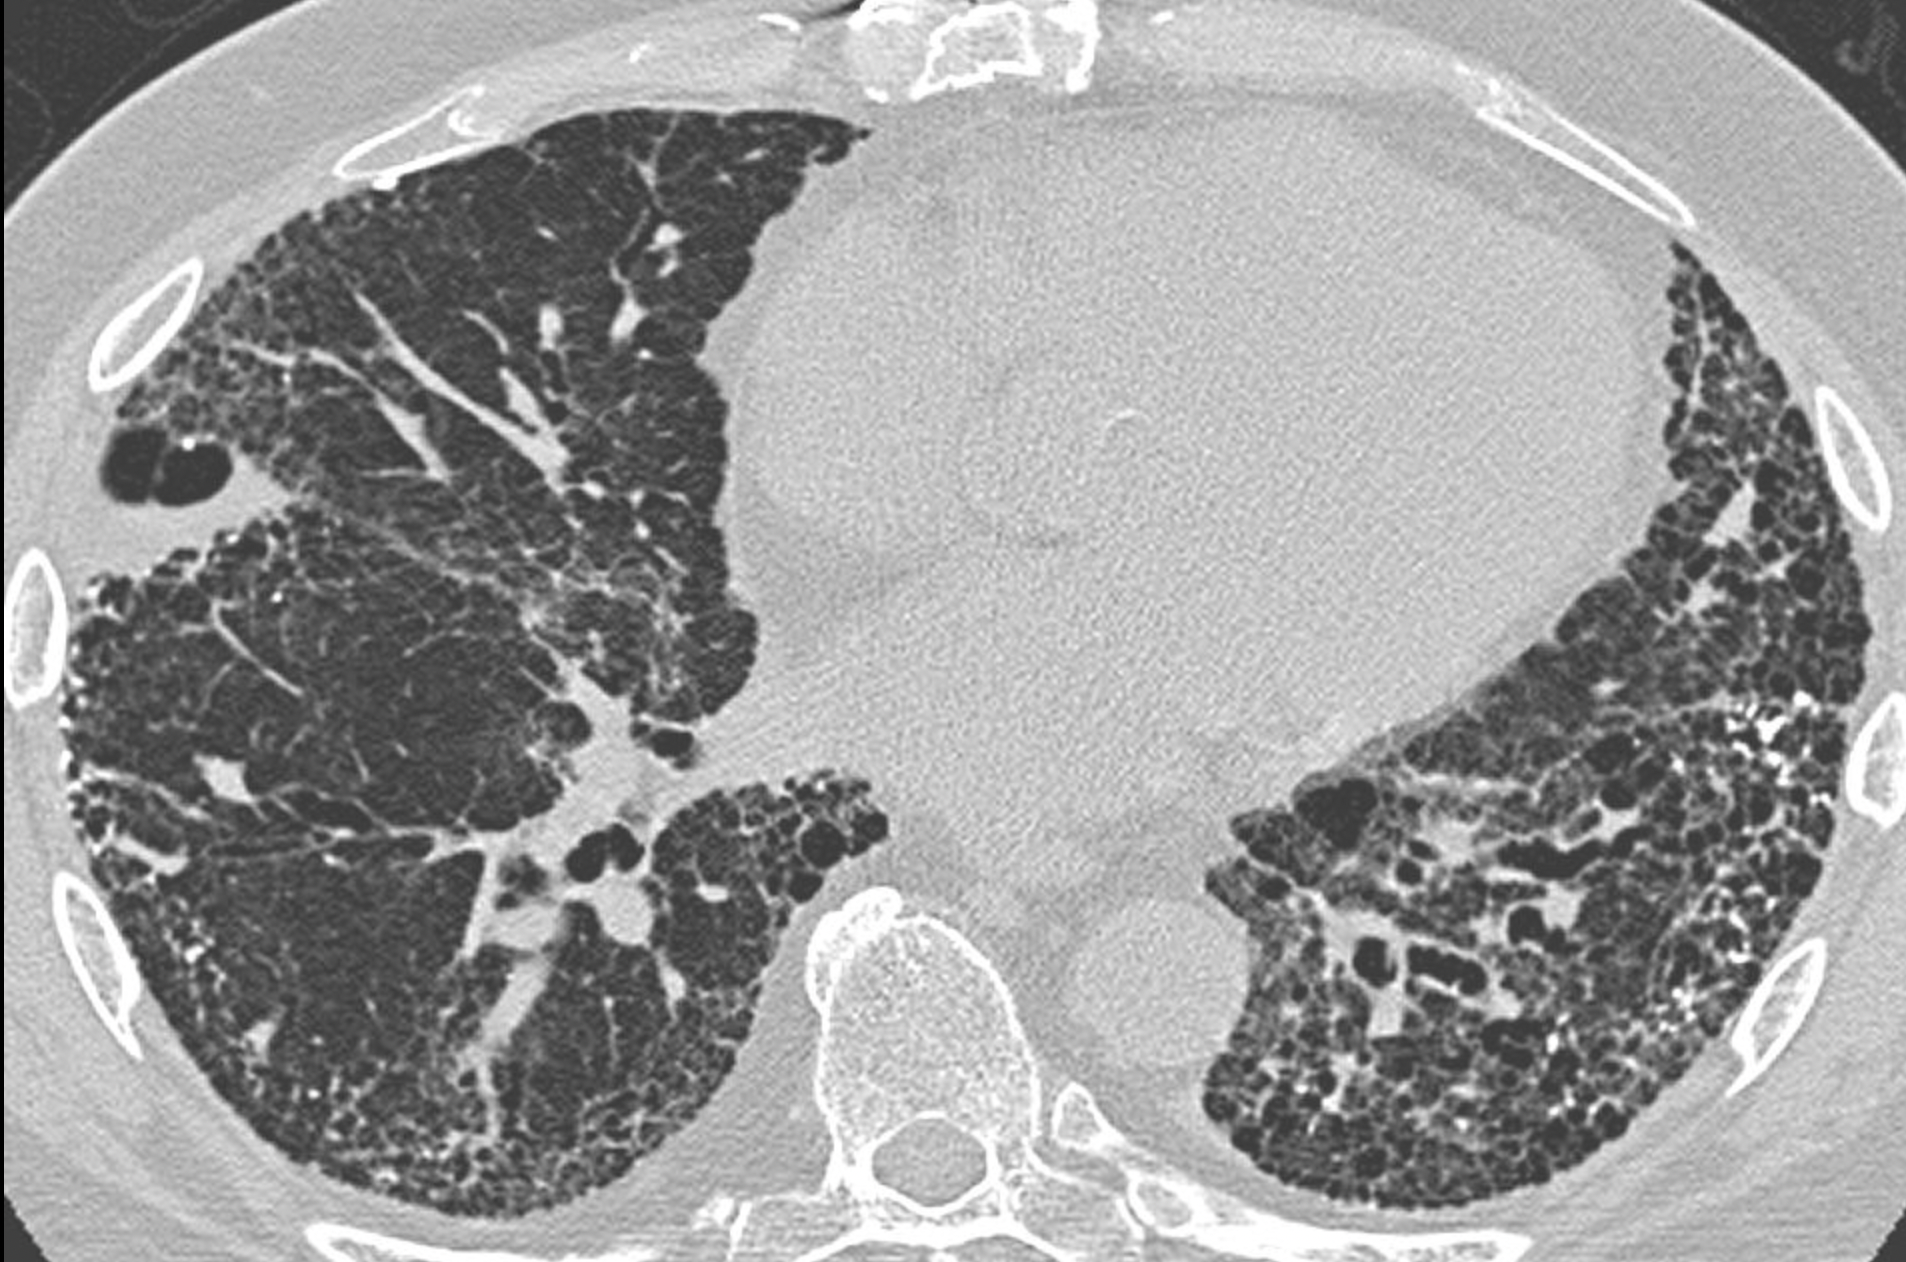

• High-resolution CT chest:

• UIP (usual interstitial pneumonia) pattern: honeycombing (> 5% of lung parenchyma), reticular opacity (dominant) and ground-glass opacity (less extensive than reticular pattern) → carries a poor prognosis (50% survival at 3-4 years)

• NSIP (Non-specific interstitial pneumonia) pattern: bilateral ground glass opacity (dominant), reticular opacity (less extensive), usually absence of honeycombing → carries a better prognosis (divided into fibrotic and cellular subtypes → 90% survival at 5 years if cellular type or 60% at 5 years if fibrotic type)

• CT scan in a patient with usual interstitial pneumonia, showing interstitial thickening, architectural distortion, honeycombing and bronchiectasis. (courtesy of Darel Heitkamp, MD, wikipedia.org)